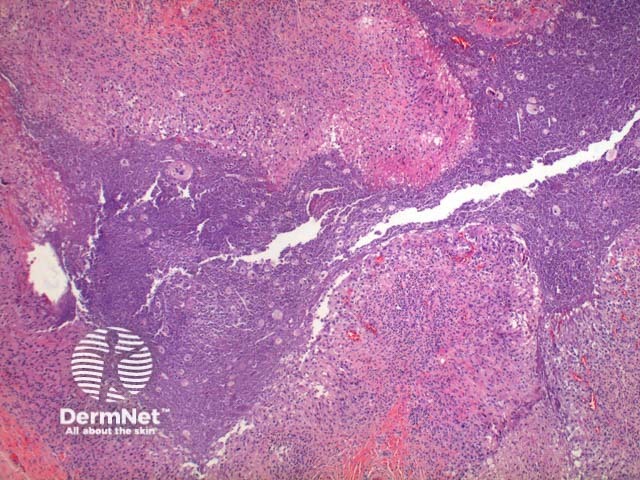

Scanning power view of phaeohyphomycosis shows a deeply extending granulomatous pattern (Figure 1) which may show areas of necrosis (Figure 2). Centrally an abscess or cystic nodule may form. Frequently a foreign body such as a wood splinter can be seen. The epidermis commonly shows pseudoepitheliomatous hyperplasia. The inflammatory infiltrate is comprised of histiocytes with multinucleated giant cells, and numerous neutrophils (Figures 3,4 and 5). At high power branching septate pigmented fungal hyphae can be seen (Figure 6).

Figure 2